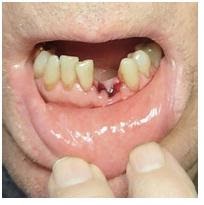

TRAUMA:- Trauma refers to injury to hard and soft tissues in the oral cavity and the face. Generally, more common in children but can occur at any age. It also requires immediate treatment.

OROFACIAL SWELLING:- Abnormal enlargement of facial tissue caused by infection, inflammation or trauma. It can be intraoral or extraoral. It should be treated as soon as possible as it can be a cause of severe infection.